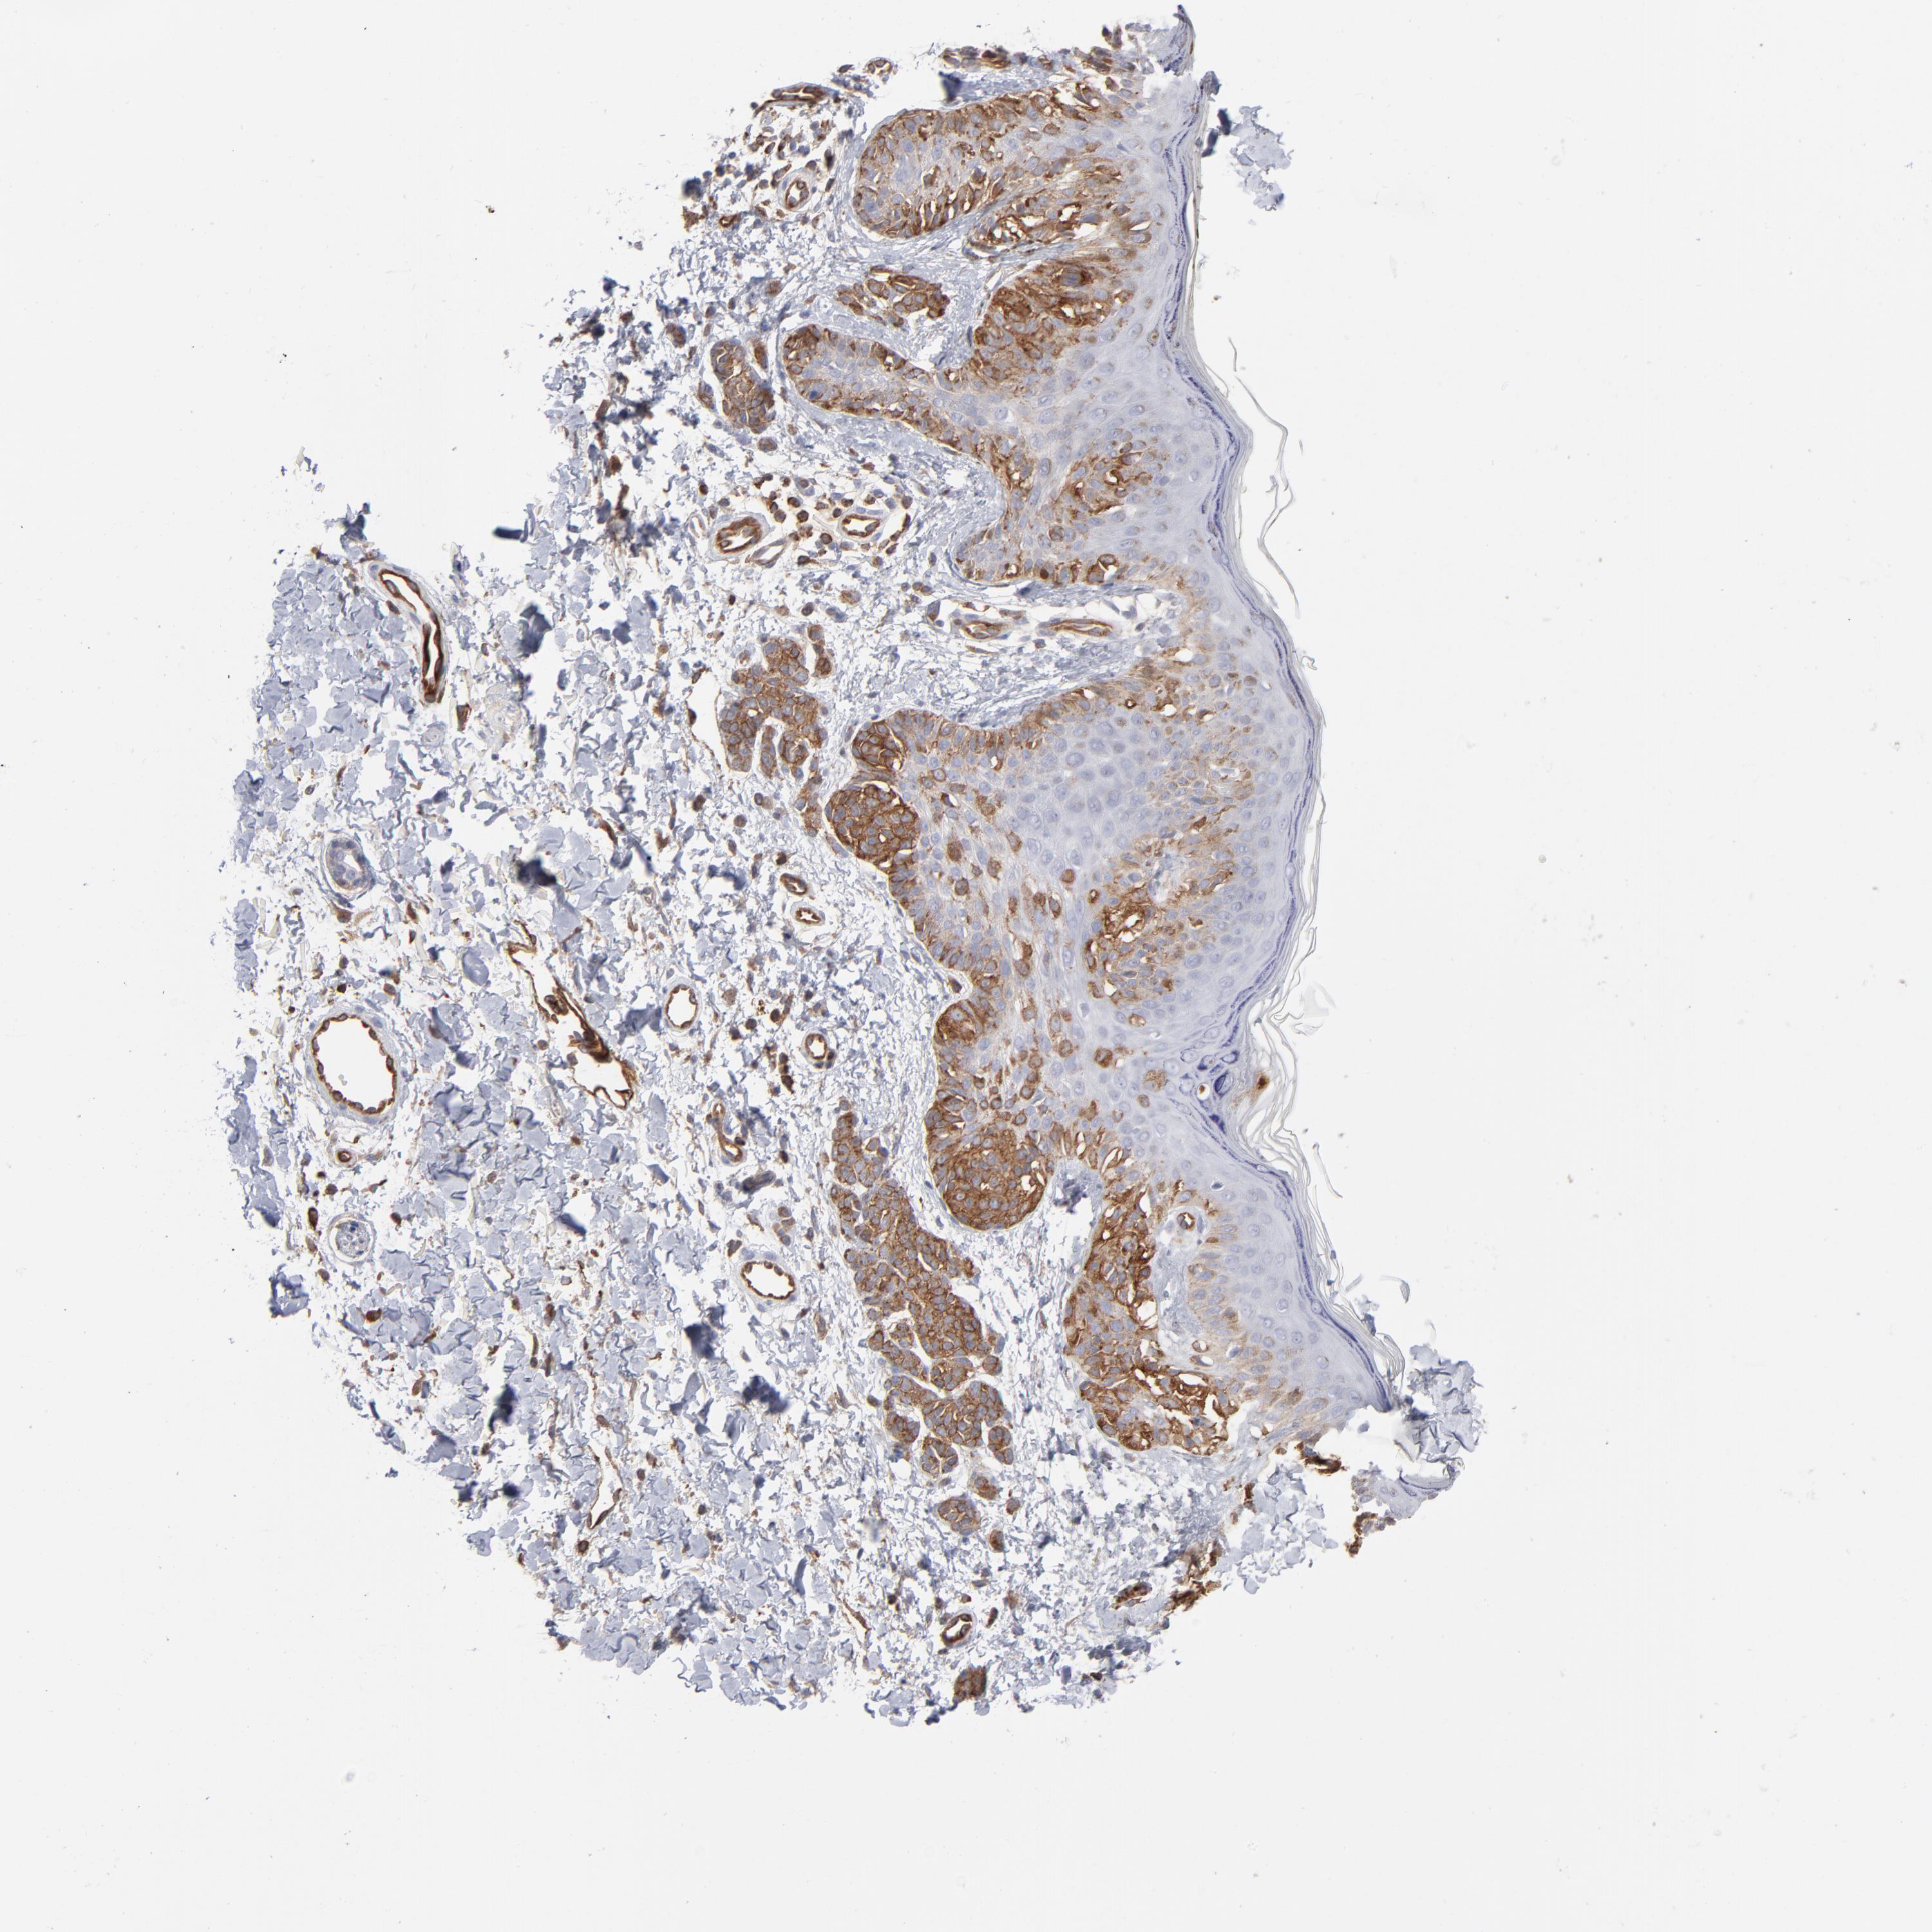

MELANOMA - Protein expressioni

A mouse-over function shows sample information and annotation data. Click on an image to view it in a full screen mode. Samples can be filtered based on level of antibody staining by selecting one or several of the following categories: high, medium, low and not detected. The assay and annotation is described here.

Note that samples used for immunohistochemistry by the Human Protein Atlas do not correspond to samples in the TCGA dataset.

Antibody stainingi

Antibody staining in the annotated cell types in the current human tissue is reported as not detected, low, medium, or high, based on conventional immunohistochemistry profiling in selected tissues. This score is based on the combination of the staining intensity and fraction of stained cells.

Each image is clickable and will lead to virtual microscopy that enables deeper exploration of all samples and also displays staining intensity scores, fraction scores and subcellular localization as well as patient and tissue information for each sample.

Antibody CAB003841

Staining

High

Medium

Low

Not detected

Intensity

Strong

Moderate

Weak

Negative

Quantity

>75%

75%-25%

<25%

None

Location

Nuclear

Cytoplasmic/membranous

Cytoplasmic/membranous,nuclear

Malignant melanoma, NOS

Malignant melanoma, Metastatic site